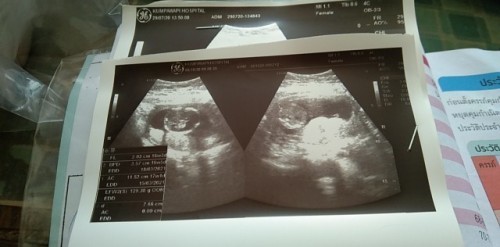

ท้องแรก15week รู้สึกดึ๊บๆนิดหน่อยนานๆๆทีค่ะ น้ำหนักลดไป3กก.ช่วงแพ้ท้อง ตอนนี้ยังไม่ขึ้นเลยค่ะ ท้องออกนิดหน่อย ซาวด์ล่าสุด13+2 น้องแข็งแรงดี โตตามเกณฑ์ ได้ลูกชายค่า